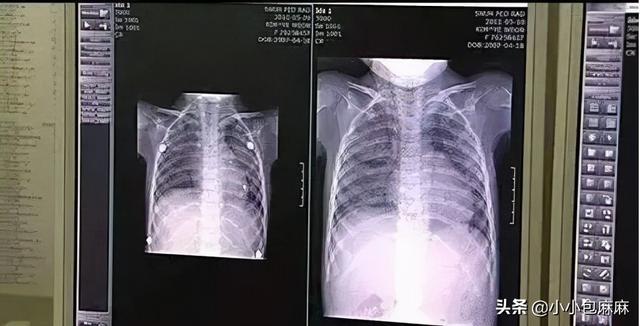

加湿器用了不到一夜,家里3个孩子齐刷刷进了医院,被确诊为肺炎。

很多“加湿器肺炎”也是这么来的!